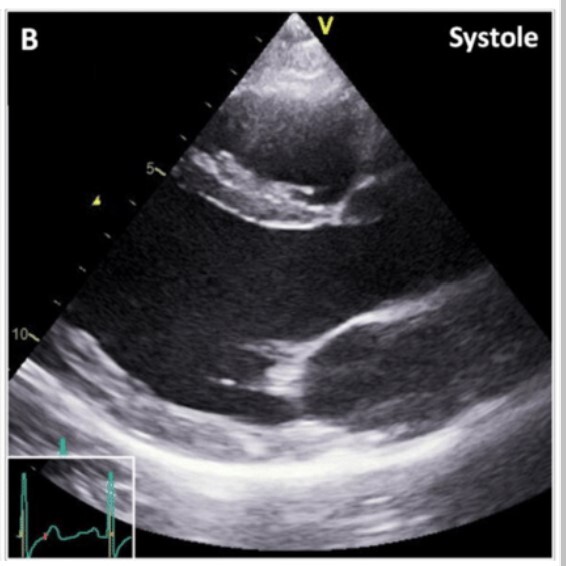

Apical 4 chamber view - put probe in inframammary crease put probe indicator on the left and angle medially. Possibly best view for evaluating mitral valve function especially with doppler.